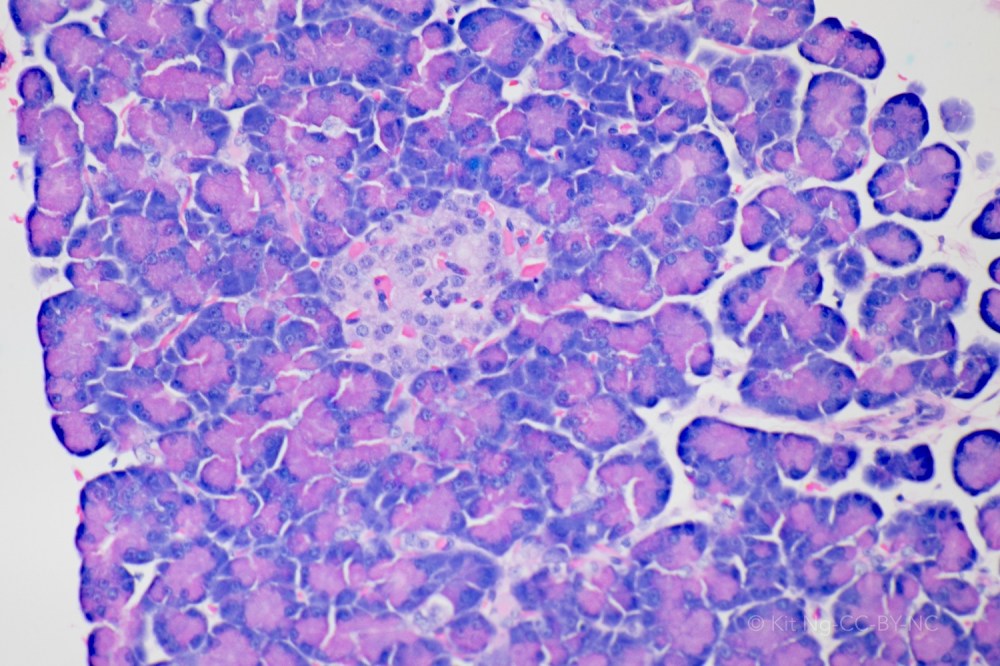

The pancreas is a retroperitoneal organ located behind the stomach. The organ is organized into lobes. The relationship between the pancreas and other organs can be viewed in the model here. Microscopically the organ has two parts – the endocrine part consists of the Islets of Langerhans, and the exocrine part consists of the acini.

The Acini portion produces the precursor to digestive enzymes (Zymogens) for the chemical digestion of nutrients. These enzymes include proteases, pancreatic amylase, lipase, and nuclease. These enzymes are mixed with the bicarbonate fluid produced by the ducts and collectively known as pancreatic juice. This pancreatic juice is secreted into the major and accessory pancreatic ducts. In particular, the major pancreatic duct (Duct of Wirsung) joins with the common bile duct at the hepatopancreatic ampulla (Ampulla of Vater). This ampulla is located at the major duodenal papilla in the duodenum. The release of the mixture is controlled by the hepatopancreatic sphincter (Sphincter of Oddi) that is regulated by the hormone Cholecystokinin to aid in the chemical digestion in the small intestine.